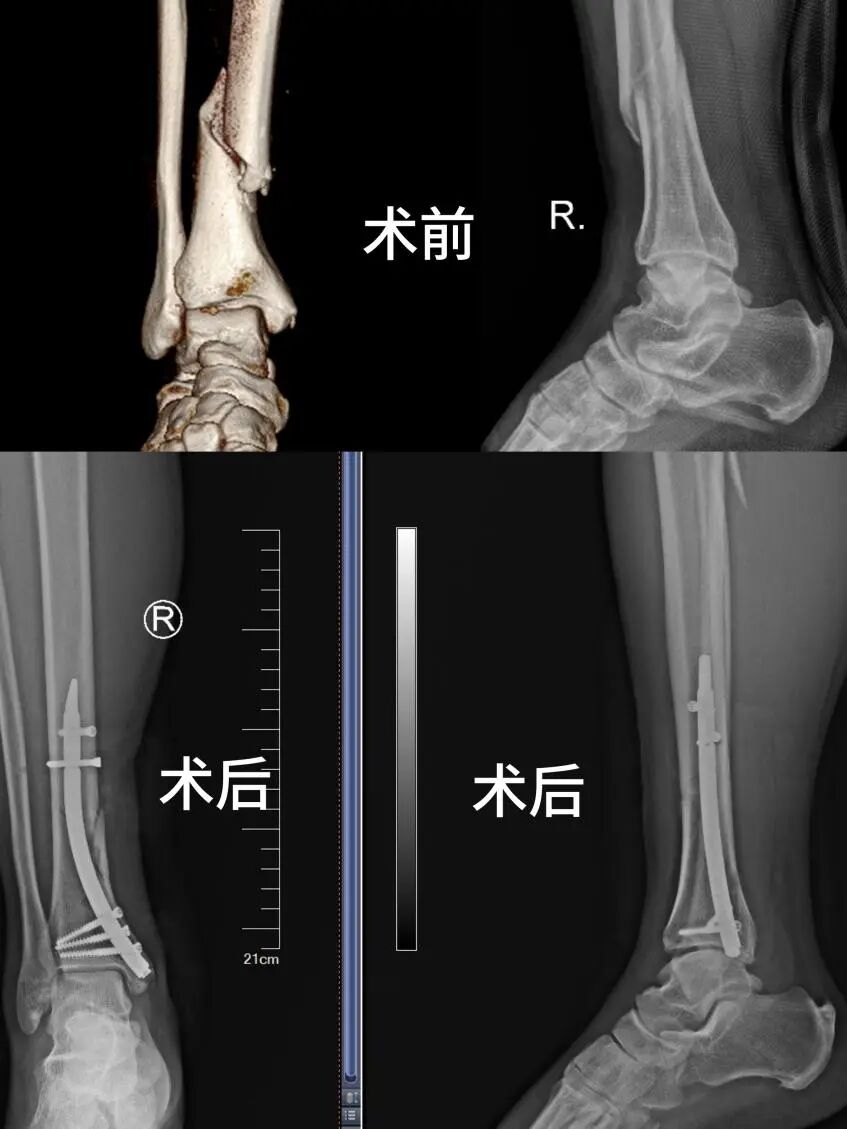

半岛网4月2日讯 (记者 纪豪杰)近日,青岛市海慈中医医疗集团创伤骨科与手足外科团队成功运用胫骨内踝逆行髓内针技术,为一名51岁右胫骨中下段螺旋形骨折患者完成微创内固定手术。这一技术的成功落地,标志着青岛市海慈中医医疗集团在四肢骨折微创治疗领域再获新突破,为岛城及周边地区骨折患者带来了更加精准、安全、高效的治疗新选择。

患者因不慎扭伤导致右胫骨中下段骨折,入院后影像学检查提示骨折呈螺旋形,伴有明显粉碎倾向。这类骨折在临床上处理难度较大,不仅骨折端不稳定,而且胫骨中下段软组织覆盖薄弱、血运较差,传统治疗方案往往面临不小的挑战。如果采用传统切开复位钢板内固定,一方面手术切口较长、软组织剥离范围大,术中出血多,术后存在较高的皮肤坏死、切口愈合不良、感染等风险;另一方面,钢板属于偏心固定,对于螺旋形、粉碎性骨折的把持力相对不足,容易发生内固定失败或骨折延迟愈合。

术中严格遵照术前设计,各环节衔接紧密、有条不紊,术中仅在内踝处切开一个约2厘米的小切口,在C型臂X光机透视引导下精准置入髓内针,实现了对骨折端的中心性固定。整个手术过程顺利,出血量极少,手术时长较传统术式明显缩短。术后复查影像显示,骨折对位对线良好,内固定位置精准,患者肢体肿胀程度轻,皮肤血运良好,无任何并发症发生。术后第2天,患者即在医生指导下开始进行踝关节及膝关节功能锻炼,为早期功能康复奠定了良好基础,患者及家属对治疗效果给予高度评价。